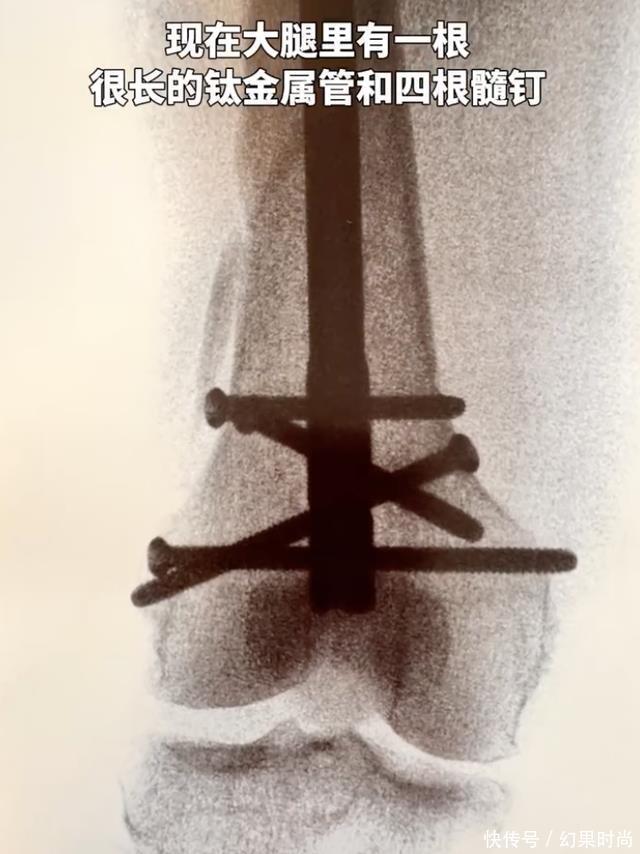

向太这次摔得不轻,获胜骨折,阅历了五个小时的手术,骨头里安了一根很长的钛金属管和四根髓钉,向太幽默地自称是钢铁女侠。好多老东说念主齐是因为跌倒而蓦然在世,幸亏向太莫得人命危急。